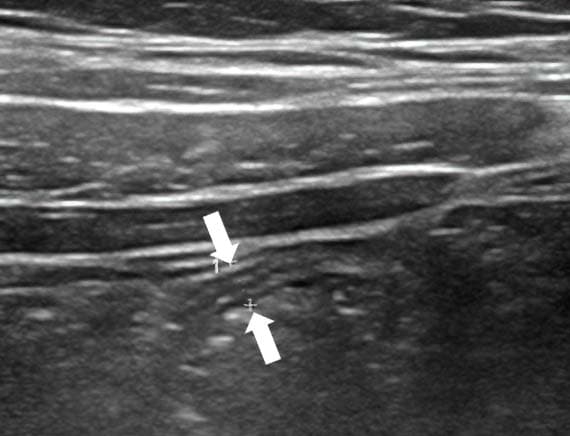

Аппендикс считается расширенным, если под действием компрессии его наружный переднезадний размер, измеренный при поперечном сканировании, более 6 мм (см. рис. 3).

Рисунок 3. Определение диаметра аппендикса.